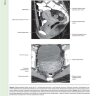

Книга содержит большое количество тщательно отобранных рисунков и фотографий с комментариями, которые показывают взаимосвязь между различными методами лучевой диагностики в гинекологии (УЗИ, в том числе трехмерным, соногистерографией, МРТ, ПЭТ/КТ) и макроскопической картиной.

Мы рады представить читателям второе издание книги «Диагностическая визуализация в гинекологии», наиболее полное руководство по методам визуальной диагностики заболеваний женской половой сферы. Более 2500 рисунков и фотографий с тщательно составленными комментариями, которые показывают взаимосвязь между различными методами лучевой диагностики в гинекологии (УЗИ, в том числе трехмерным, соногистерографией, гистеросальпингографией, МРТ, ПЭТ/ КТ) и макроскопической картиной. Для облегчения поиска и изучения материала заболевания сгруппированы в соответствии с пораженным органом: телом матки, ее шейкой, влагалищем и вульвой, яичниками, маточными трубами, тазовым дном - и включают весь спектр патологии - от врожденных аномалий развития, инфекционных и воспалительных заболеваний до злокачественных и доброкачественных опухолей. В отдельный раздел вынесены сочетанные поражения.